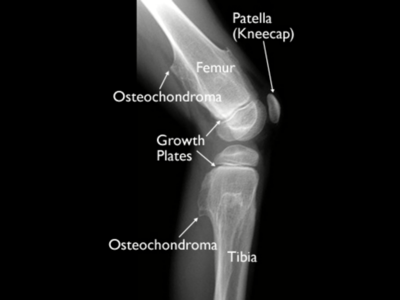

Extra Bones

These accessory bones are usually weaker than their normal anatomic counterparts, and can be injured more easily, but without them your tendon would have not where to attach itself to. If this were to case, you would not have function of that joint and or limb.